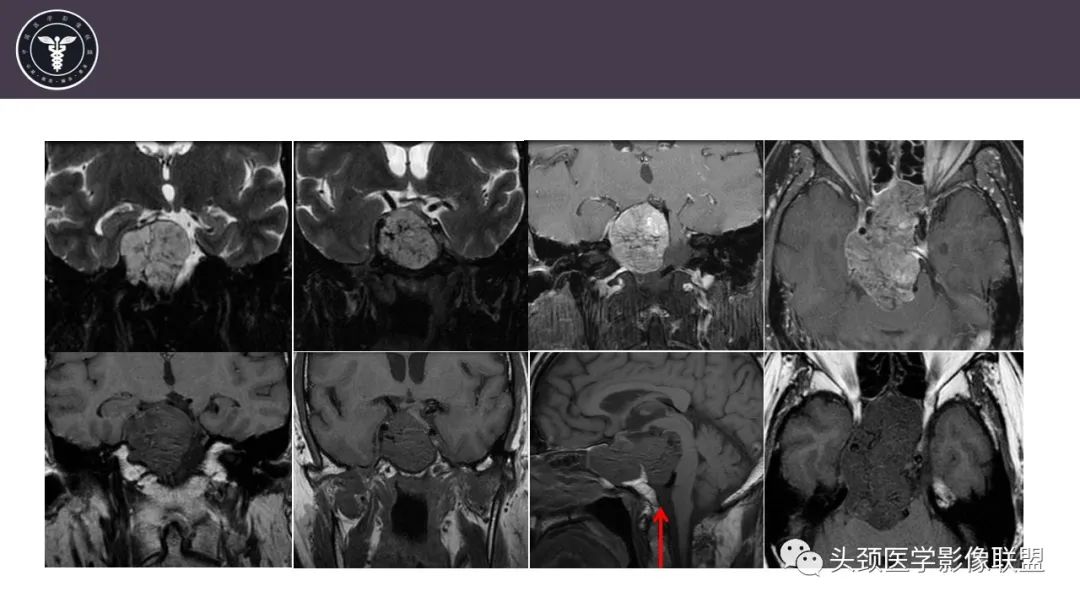

斜坡区骨巨细胞瘤 VS 脊索瘤